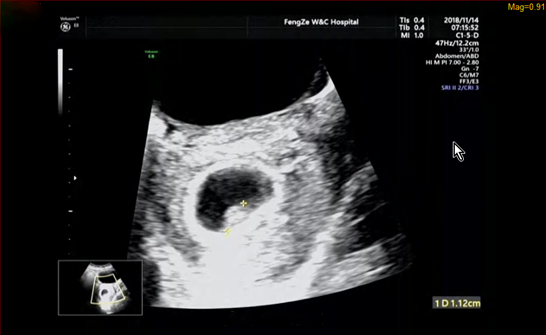

今天住院,早上測了胎心不太好,然后直接到了8樓辦住院,正好是推的預產期,兩個小時辦了手續,各種檢查,血、尿、B超、宮頸,開了兩指,